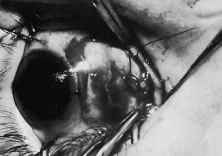

A Stevens' tenotomy hook is passed by the surgeon into the incision and is rotated so that it can be slid underneath the muscle insertion with the tip of the hook held tangential to the globe (Fig. 12). The hook should be passed 2 to 3 mm posterior to the expected location of the muscle insertion. Care is taken not to incorporate intramuscular septum or other adventitial tissue on the hook. When the lateral rectus muscle is secured with the Stevens' or Jameson muscle hook, care should be taken not to bring the inferior oblique muscle up to the insertion (Fig. 13). When the muscle is secured with the Stevens' hook, the hook and the inferior edge of the muscle insertion are elevated and a Jameson muscle hook is passed between the tented muscle tissue and the sclera to secure the muscle at its insertion (Fig. 14). Care is taken to include the entire insertion of the tendon on the hook. The tip of the Jameson hook is gently elevated by depressing the heel of the hook. This maneuver helps to ensure that the entire tendon of the muscle remains captured on the hook. A Stevens' tenotomy hook is placed in the incision, this time anterior to the insertion beneath the conjunctiva (Fig. 15). The Stevens' hook is passed posterior over the orbital surface of the muscle (Fig. 16). Gentle pressure on the Stevens' hook is directed posterior so that the check ligaments and Tenon's tissue that overlie the muscle belly are separated from the muscle capsule with blunt dissection. The hook usually is passed posterior for about 10 mm. When recessing a lateral rectus, attachments between the underside of the lateral rectus and inferior oblique are broken (Fig. 17). Two or three passes over the muscle are made, and, with simultaneous countertraction on the Stevens' hook and the Jameson hook, the conjunctiva is elevated and pulled over the tip of the Jameson hook (Fig. 18A and B).

|

The intermuscular septum and Tenon's capsule at the ball-like tip of the Jameson hook are incised with a Westcott scissors (Fig. 19). A Manhattan forceps can be used to elevate the intramuscular and Tenon's tissue to facilitate this step. Care is taken to incorporate the entire muscle tendon on the Jameson hook before this cut is made. If it is evident that there is residual tendon that is not placed on the hook, the additional tendon, intramuscular septum, and anterior Tenon's tissue are reflected over the tip of the Jameson hook with the closed tips of the Westcott scissors or a small muscle hook.

A Stevens' hook is inserted in the opening in the intermuscular septum created by the scissors and is passed anterior to the insertion. Parks has referred to this maneuver as the “pole test.” This maneuver is done to verify that the tendon of the muscle has not been split and that the complete muscle tendon is incorporated on the hook. Leaving residual slips of muscle tendon will partially or completely negate the effect of a recession procedure (Fig. 20A and B).